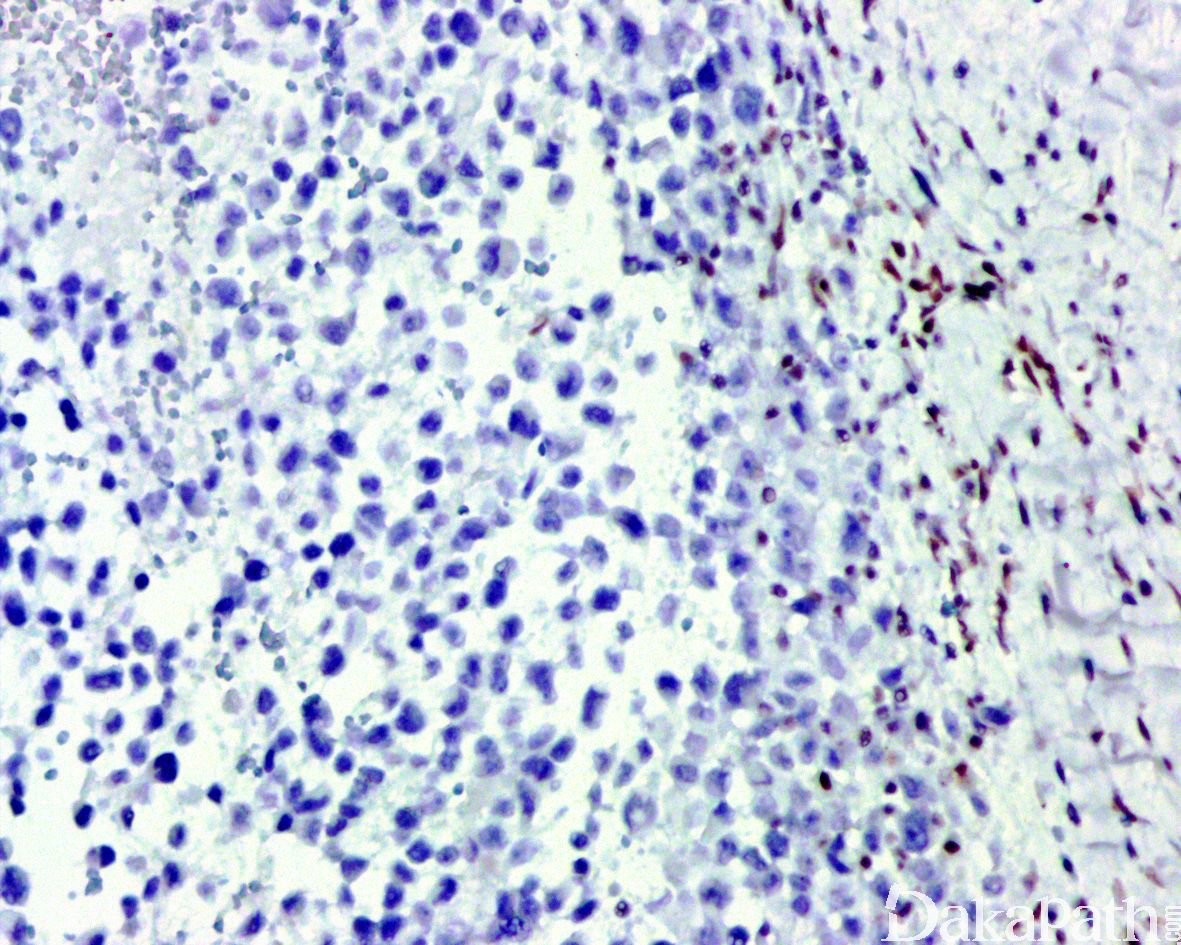

免疫组织化学染色:

瘤细胞 AE1/AE3. EMA、CK8. CK19 和 vimentin 常阳性,50%-70%病例 CD34 阳性,95%以上显示 SMARCB1(INI1)表达丢失;部分病例可表达 MSA、α-SMA、S-100. ERG 和 NSE,偶尔表达 SALL4,—般不表达 CK20. desmin、NF、CEA 和 CD31。

95%以上可见 SMARCB1 基因缺失